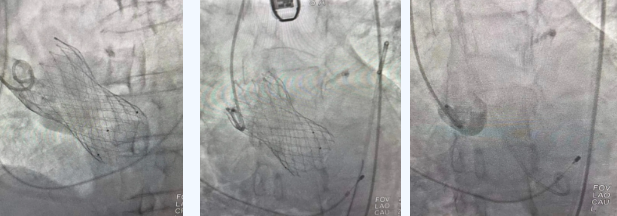

在麻醉手術(shù)中心的配合下,曾廣偉主任用導(dǎo)管經(jīng)股動(dòng)脈鞘進(jìn)入主動(dòng)脈瓣目標(biāo)位置,經(jīng)豬尾導(dǎo)管造影可見(jiàn)主動(dòng)脈瓣大量返流,因左室流出道較寬,大于瓣膜落腳點(diǎn)直徑,瓣膜釋放位置選擇及釋放難度極大。更為關(guān)鍵的是,患者常規(guī)四個(gè)錨定點(diǎn)只有一個(gè)可以用,定位要極其精準(zhǔn)才能保證瓣膜釋放后牢靠,同時(shí)不能有大的殘余瘺!稍有移位可能就需要再次植入瓣中瓣或者開刀!

術(shù)中,曾廣偉主任團(tuán)隊(duì)高效配合,完成了特定時(shí)間點(diǎn)起搏心臟、臨時(shí)短時(shí)間關(guān)閉呼吸機(jī)、降低主動(dòng)脈瓣阻力、快速釋放瓣膜等一系列高難度操作,有效保證瓣膜精準(zhǔn)釋放。瓣膜釋放經(jīng)TEE確認(rèn),主動(dòng)脈瓣膜釋放位置佳,經(jīng)豬尾導(dǎo)管造影,主動(dòng)脈瓣返流即刻消失,且無(wú)瓣周瘺。